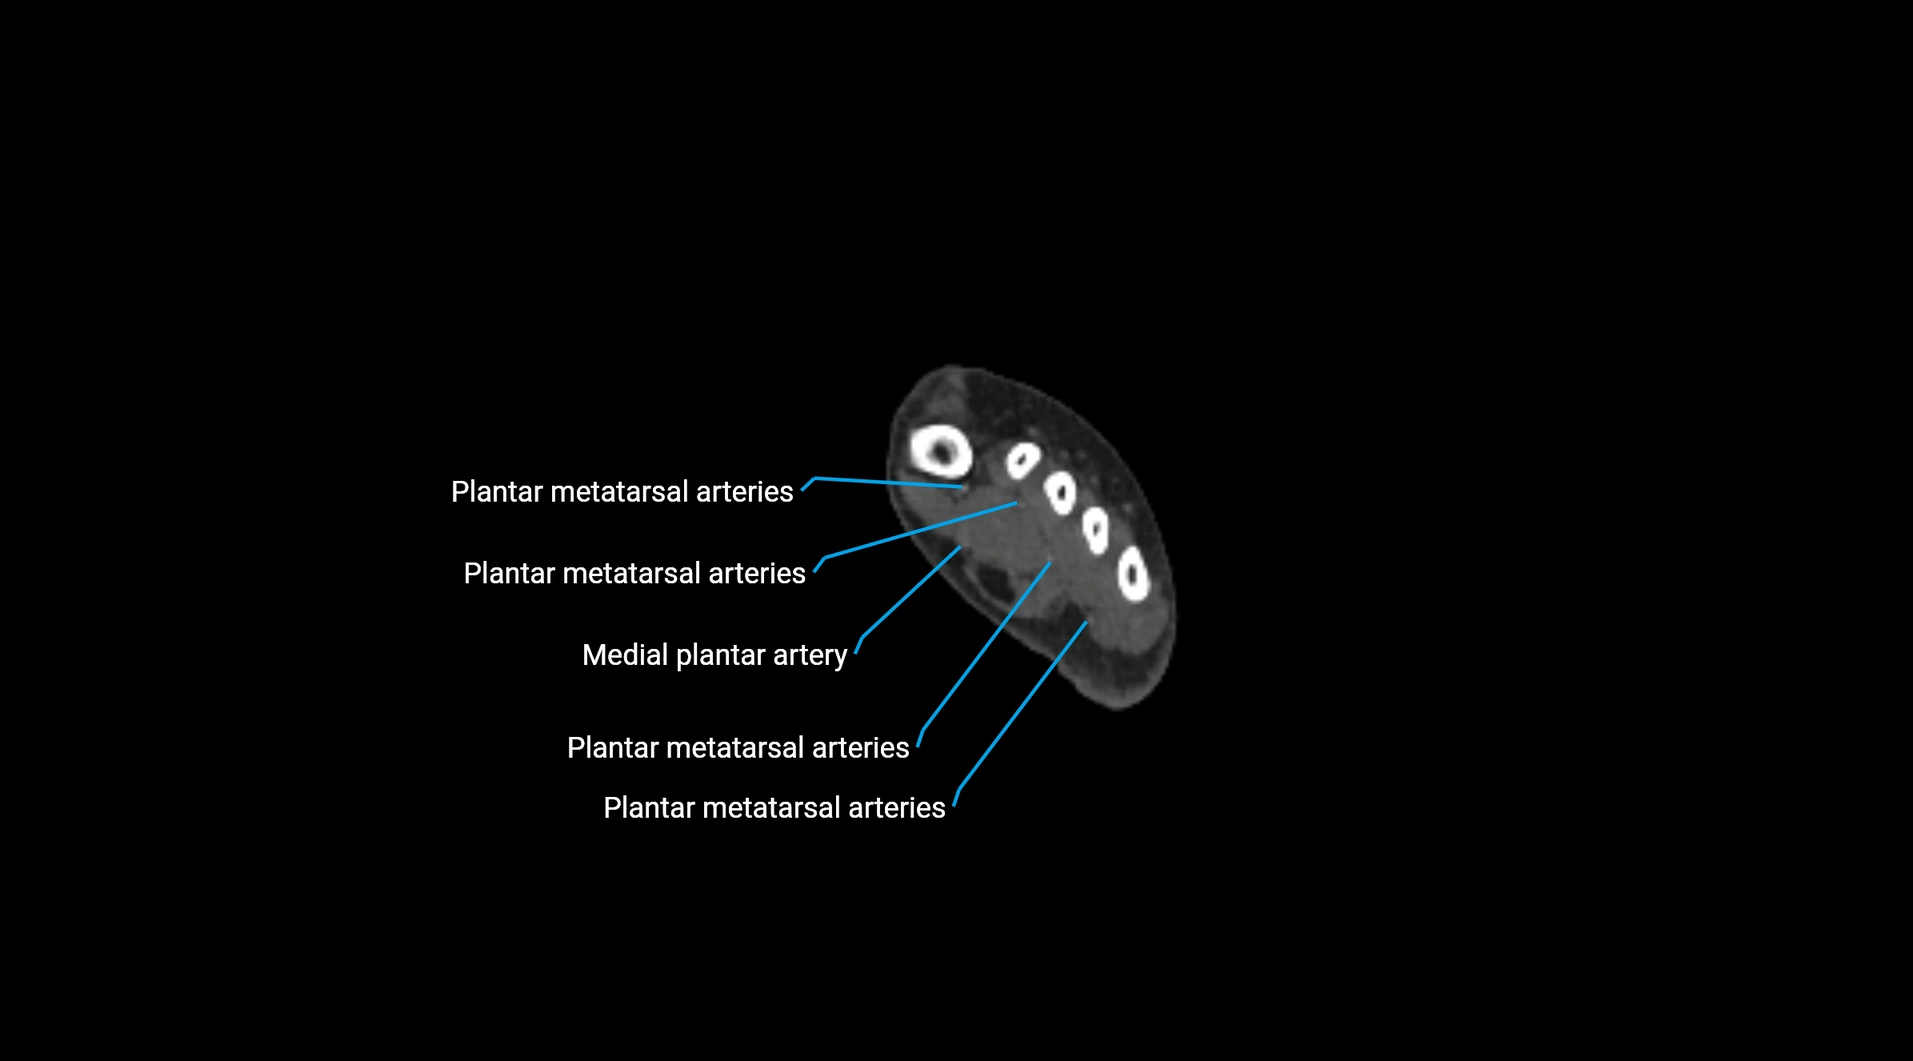

CT images

image